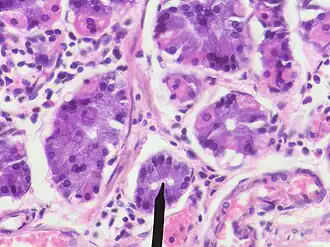

Human chief cells near tip of RED pointer | |

A gastric chief cell, peptic cell, or gastric zymogenic cell is a type of gastric gland cell that releases pepsinogen and gastric lipase. It is the cell responsible for secretion of chymosin (rennin) in ruminant animals and some other animals.[1] The cell stains basophilic upon H&E staining due to the large proportion of rough endoplasmic reticulum in its cytoplasm. Gastric chief cells are generally located deep in the mucosal layer of the stomach lining, in the fundus and body of the stomach.[2][3]

Gastric chief cells are epithelial cells which are found within the gastric unit or gastric gland, and form the base of the gastric unit.[11] The gastric chief cell has an extensive network of lamellar rough endoplasmic reticulum organized around the nucleus. The gastric chief cell also contains many large secretory vesicles filled with digestive enzymes in the apical cytoplasm.[12]